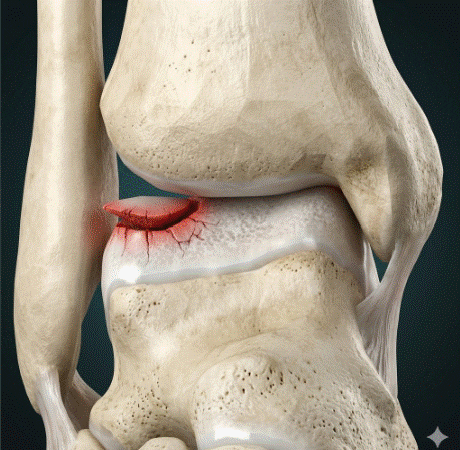

Tendinopatía rotuliana en deportistas: tratamiento y evidencia

La tendinopatía rotuliana en deportistas es una de las lesiones por sobrecarga más frecuentes y limitantes en los deportes que implican saltos repetitivos, como el baloncesto, el voleibol, el atletismo de saltos o el fútbol. Conocida popularmente como «rodilla del saltador», esta patología afecta al tendón rotuliano en su inserción en el polo inferior de […]